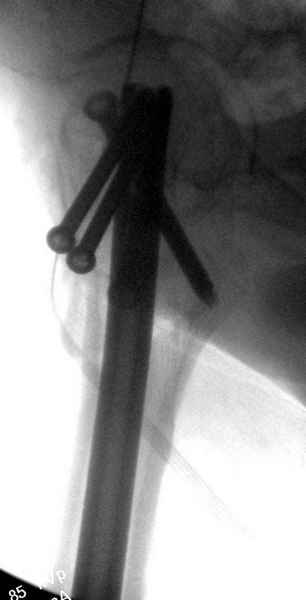

Правильно, ситуация изменилась, как говорят у нас теперь "different animal", надо решать проблему подвертельного перелома. При наличии различных вариантов фиксаторов, включая Страйкер Гамма 3, мы выбрали DePuy Antegrade Trachanteric Nail из-за многовариантности проксимальной фиксации и двойного изгиба. Вводится через вертел под 8 градусным углом, и есть достаточный передний диафизарный изгиб, предупреждающий пенетрацию дистального переднего кортекса.